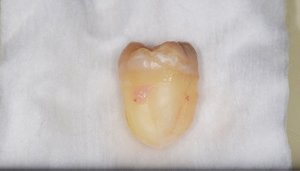

左上下の親知らずが

大きな虫歯になっていた症例

- 抜歯前写真(レントゲン、CT等)

- 抜去歯の写真

| 年齢 | 20代・女性 |

|---|---|

| 主訴 | 右下の親知らずを抜きたい |

| 親知らずの生え方 | 半分埋まっている |

| 抜歯時間 | 60分 |

| 費用 | 約6,000円(CT代含む) |

| 抜歯内容 | 右下親知らずが半分埋まっているため、汚れが溜まりやすく気になる為患者様のご希望により抜歯しました。 このケースでは事前にCTを撮影し、歯の位置、神経との位置関係を確認してから抜歯を行っています。 抜歯後、一週間は腫れと痛みがありましたが鎮痛剤を飲んで対応して頂き、糸取りをする頃には痛みや腫れは無くなり、患者様も安心しておられました。 |